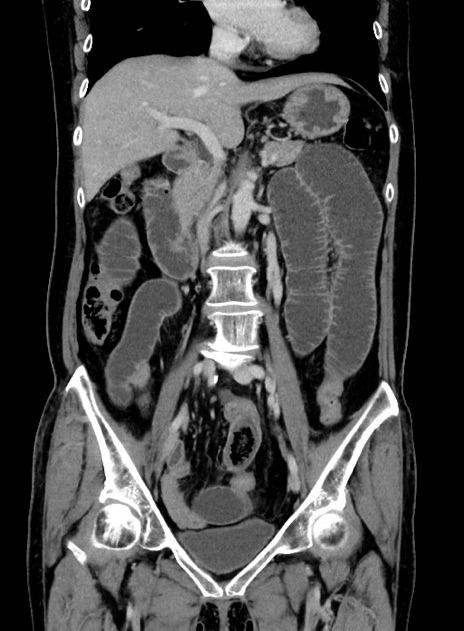

症例9(冠状断像)

【症例】 60歳代女性

【主訴】むかつき、みぞおちの痛み

【現病歴】3日前よりむかつきがあり、食事がとれない。

【既往歴】糖尿病

【身体所見】発熱なし、心窩部圧痛軽度あるも、腹膜刺激症状なし。

【データ】WBC 7400、CRP 1.92